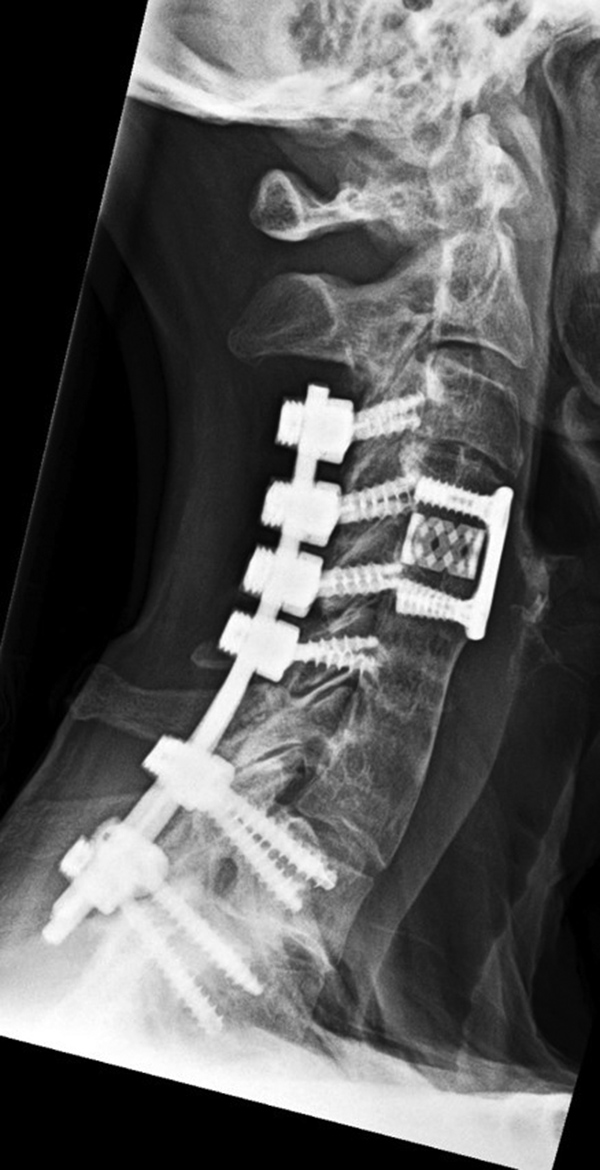

Posterior spinal wiring goes from C1 to C2. There is also solid posterior bony fusion mass from the occiput to C2 as well as an anterior cervical fusion plate and screws from C2 to C3 with interbody bony disk plug at C2-3. |